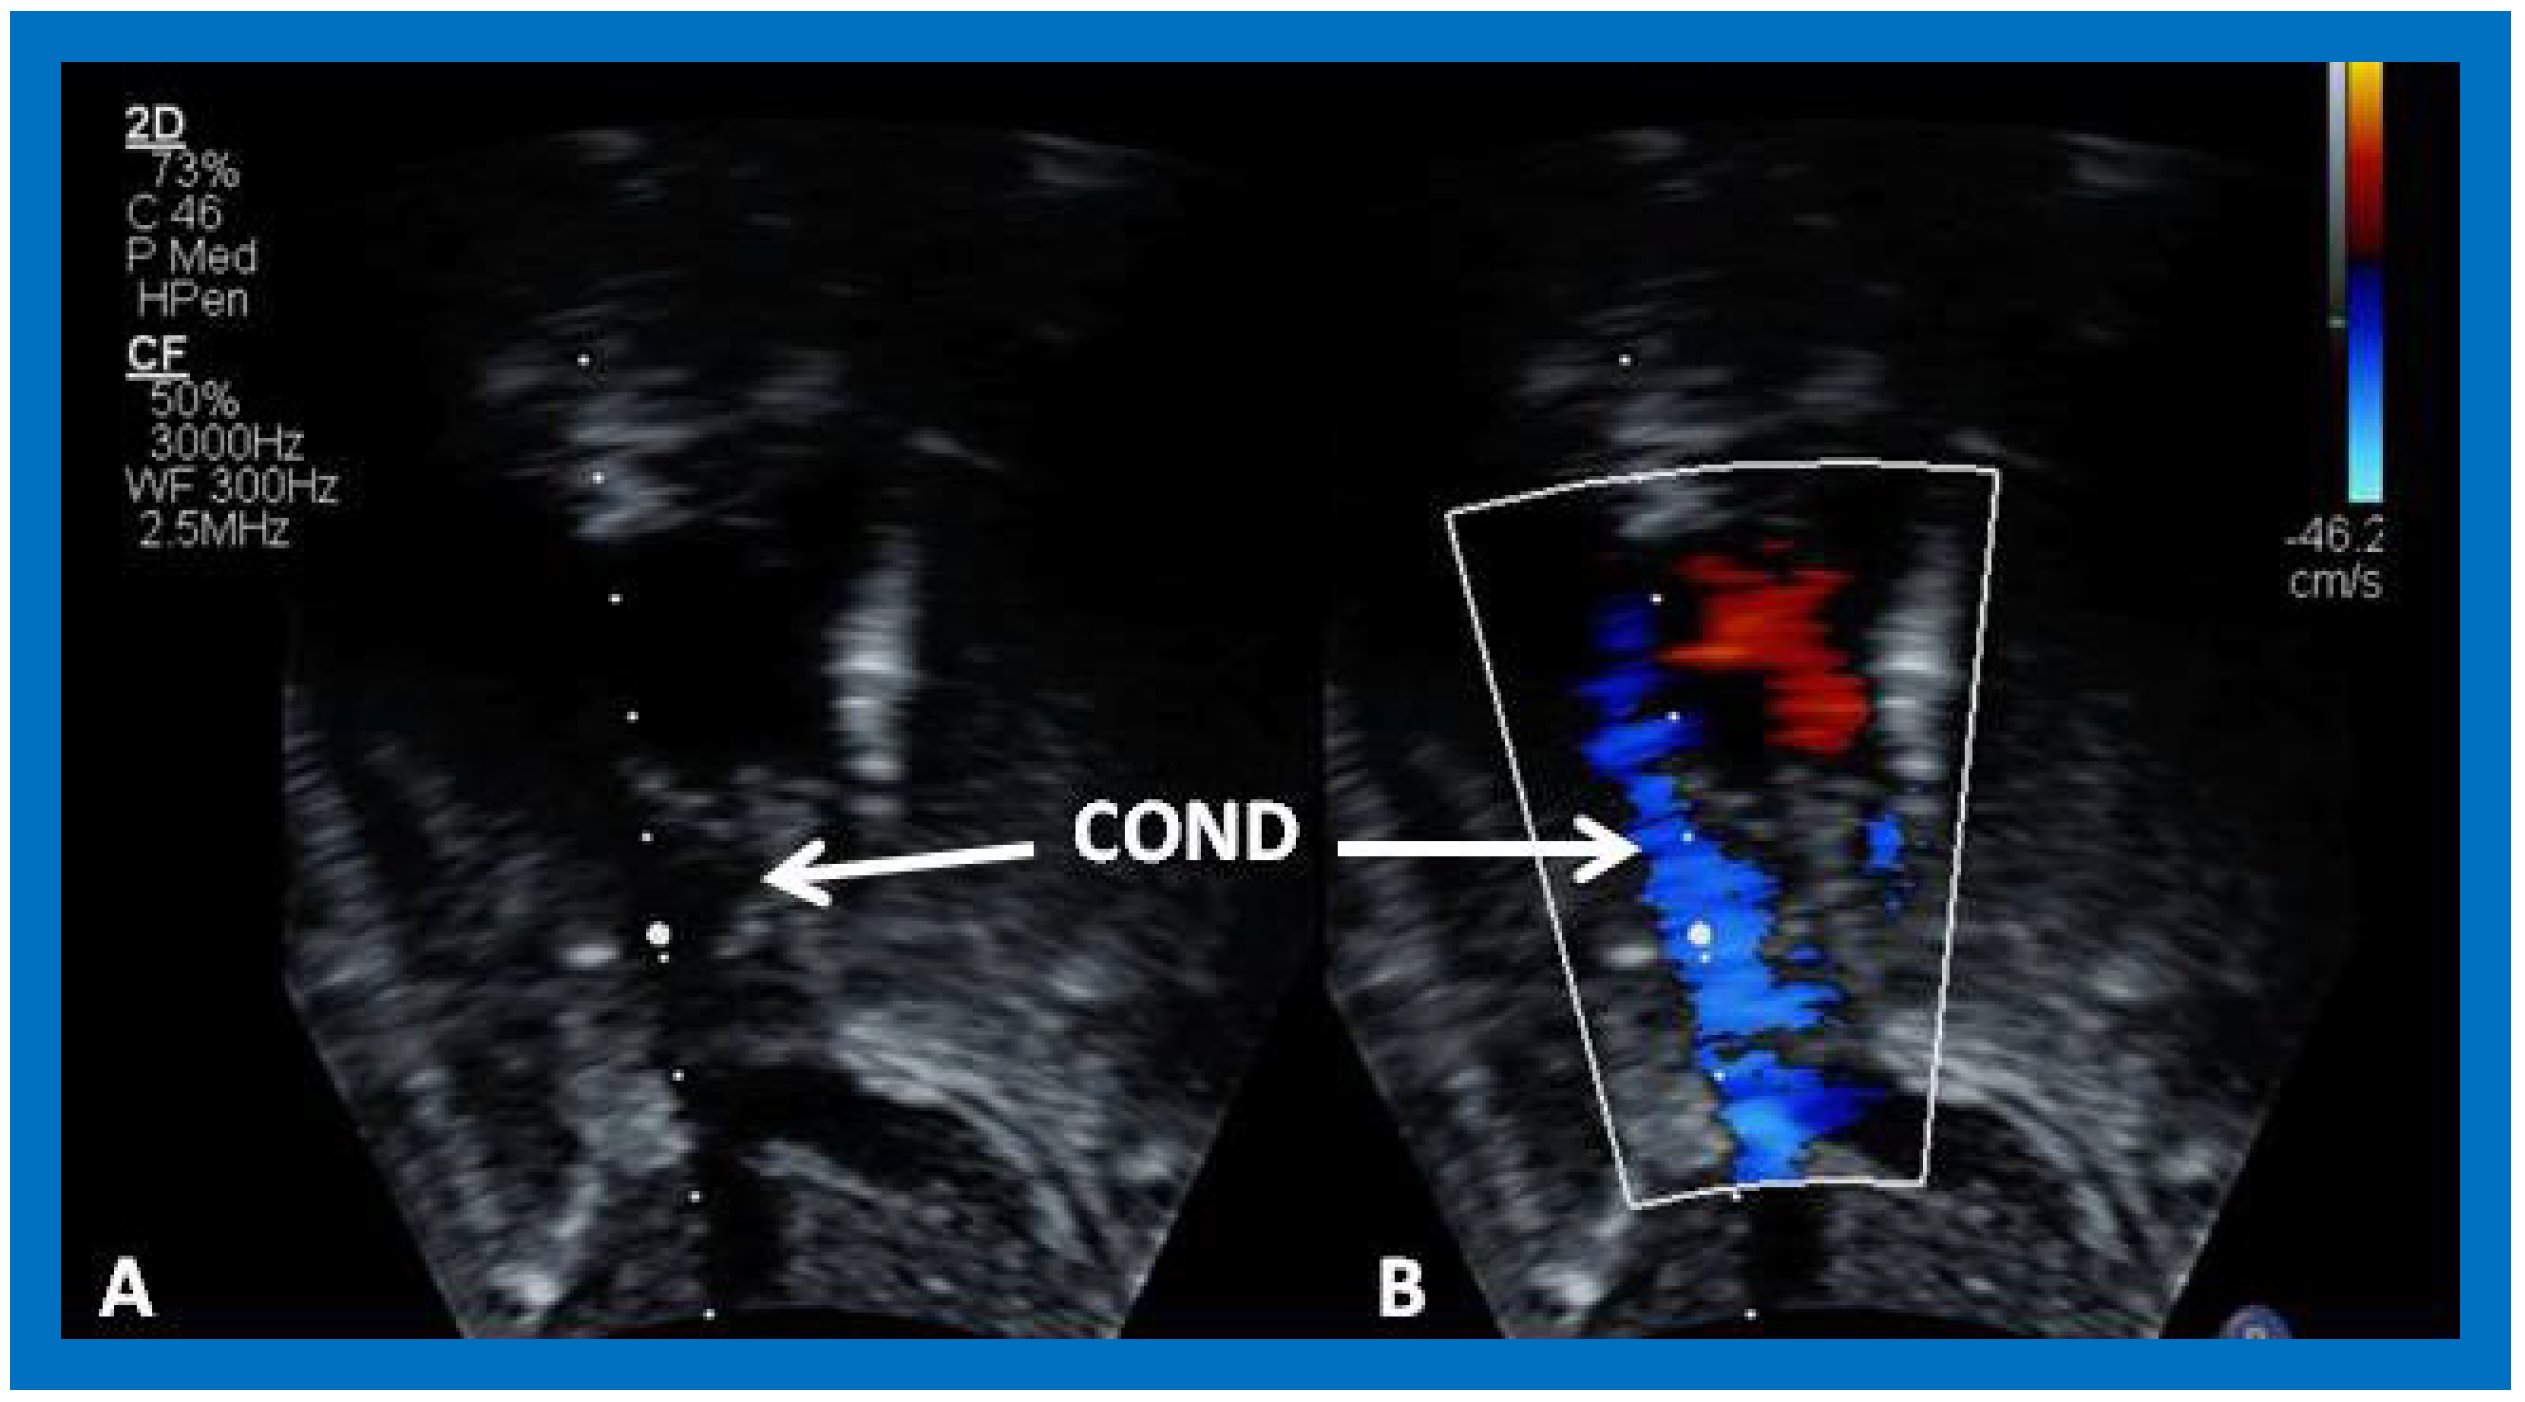

Figure 39. Selected video frame from an apical four-chamber view demonstrating the left ventricle (LV), hypoplastic right ventricle (HRV) with an atretic tricuspid valve (ATV) in a patient who had Fontan procedure. Cross-sectional view of the conduit (COND) is also shown. Note small ventricular septal defect (VSD) (long arrow).